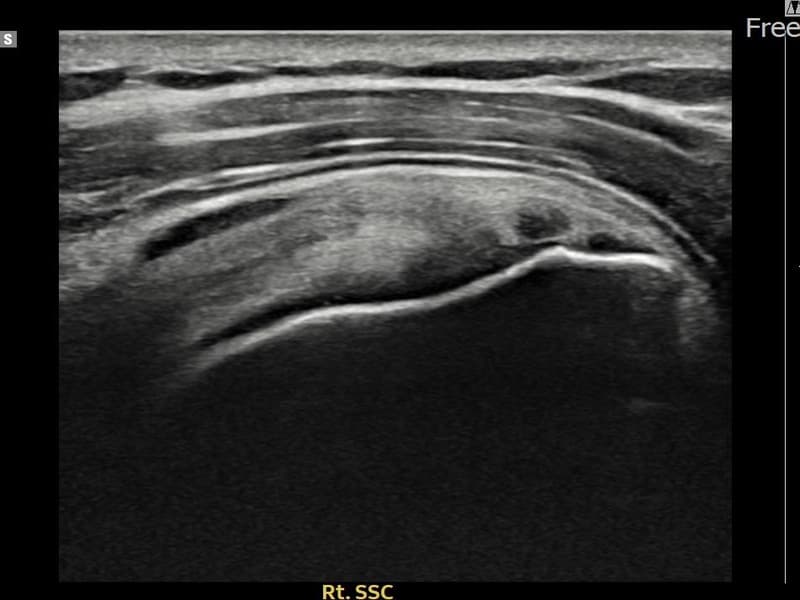

시술 전 초음파 측정 결과 파열 크기는 8mm × 3mm (힘줄 두께의 약 32% 결손)로 확인되었습니다. 시술 전 초음파에서 우측 견갑하근건 내 에코 단절과 힘줄 결손 소견이 확인되었습니다. 시술 후 초음파에서 결손 부위에 재생 조직이 채워지고 힘줄 연속성이 회복된 것이 관찰되었습니다.

30대 후반 남성 환자분으로, 우측 어깨 전방 통증이 수개월째 지속되어 내원하셨습니다. 팔을 앞으로 들어 올리거나 머리 위로 뻗는 동작 시 통증이 심하고, 무거운 것을 들거나 밀 때 어깨 앞쪽에 힘이 빠지는 느낌이 있다고 하셨습니다. 초음파 검사에서 우측 견갑하근건 부분파열이 확인되었으며, 초음파 유도 하 축소봉합술을 시행하였습니다. 시술 후 보조기 착용과 단계적 재활 운동을 진행하였고, 시술 후 추적 초음파에서 힘줄 연속성이 회복되어 어깨 기능이 정상화되었습니다.